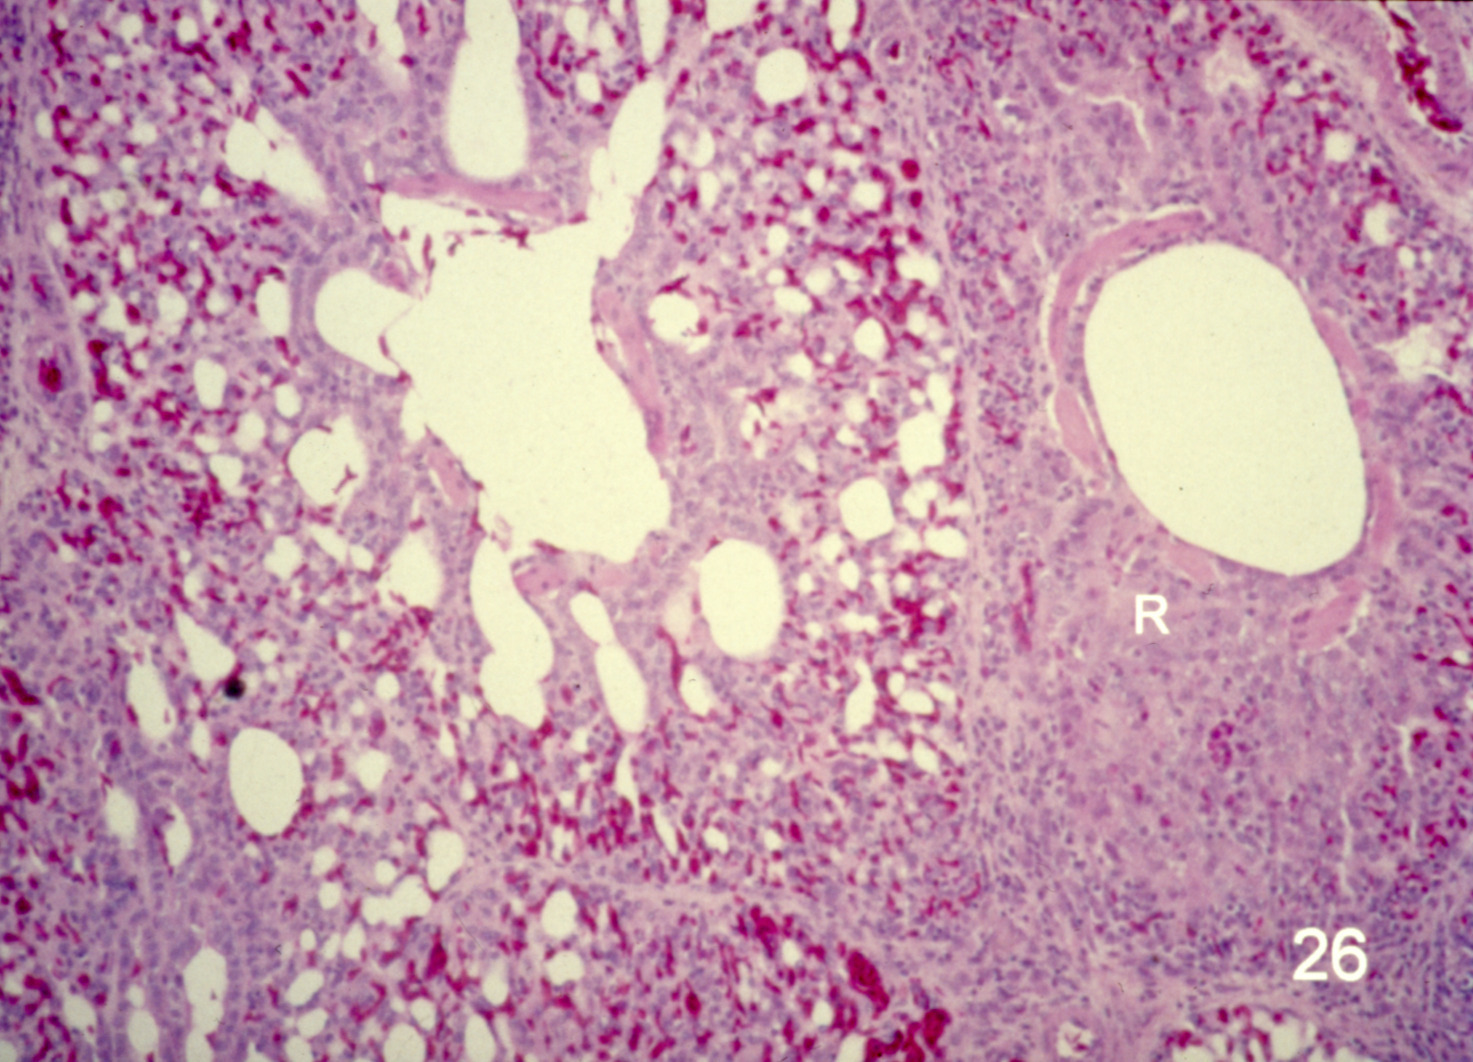

Ascites syndrome in meat-type chickens (slide study set no. 23)

Chickens--Diseases Ascites

Slide Study Set #23, Ascites Syndrome in Meat-Type Chickens (includes 27 color slides), 2001